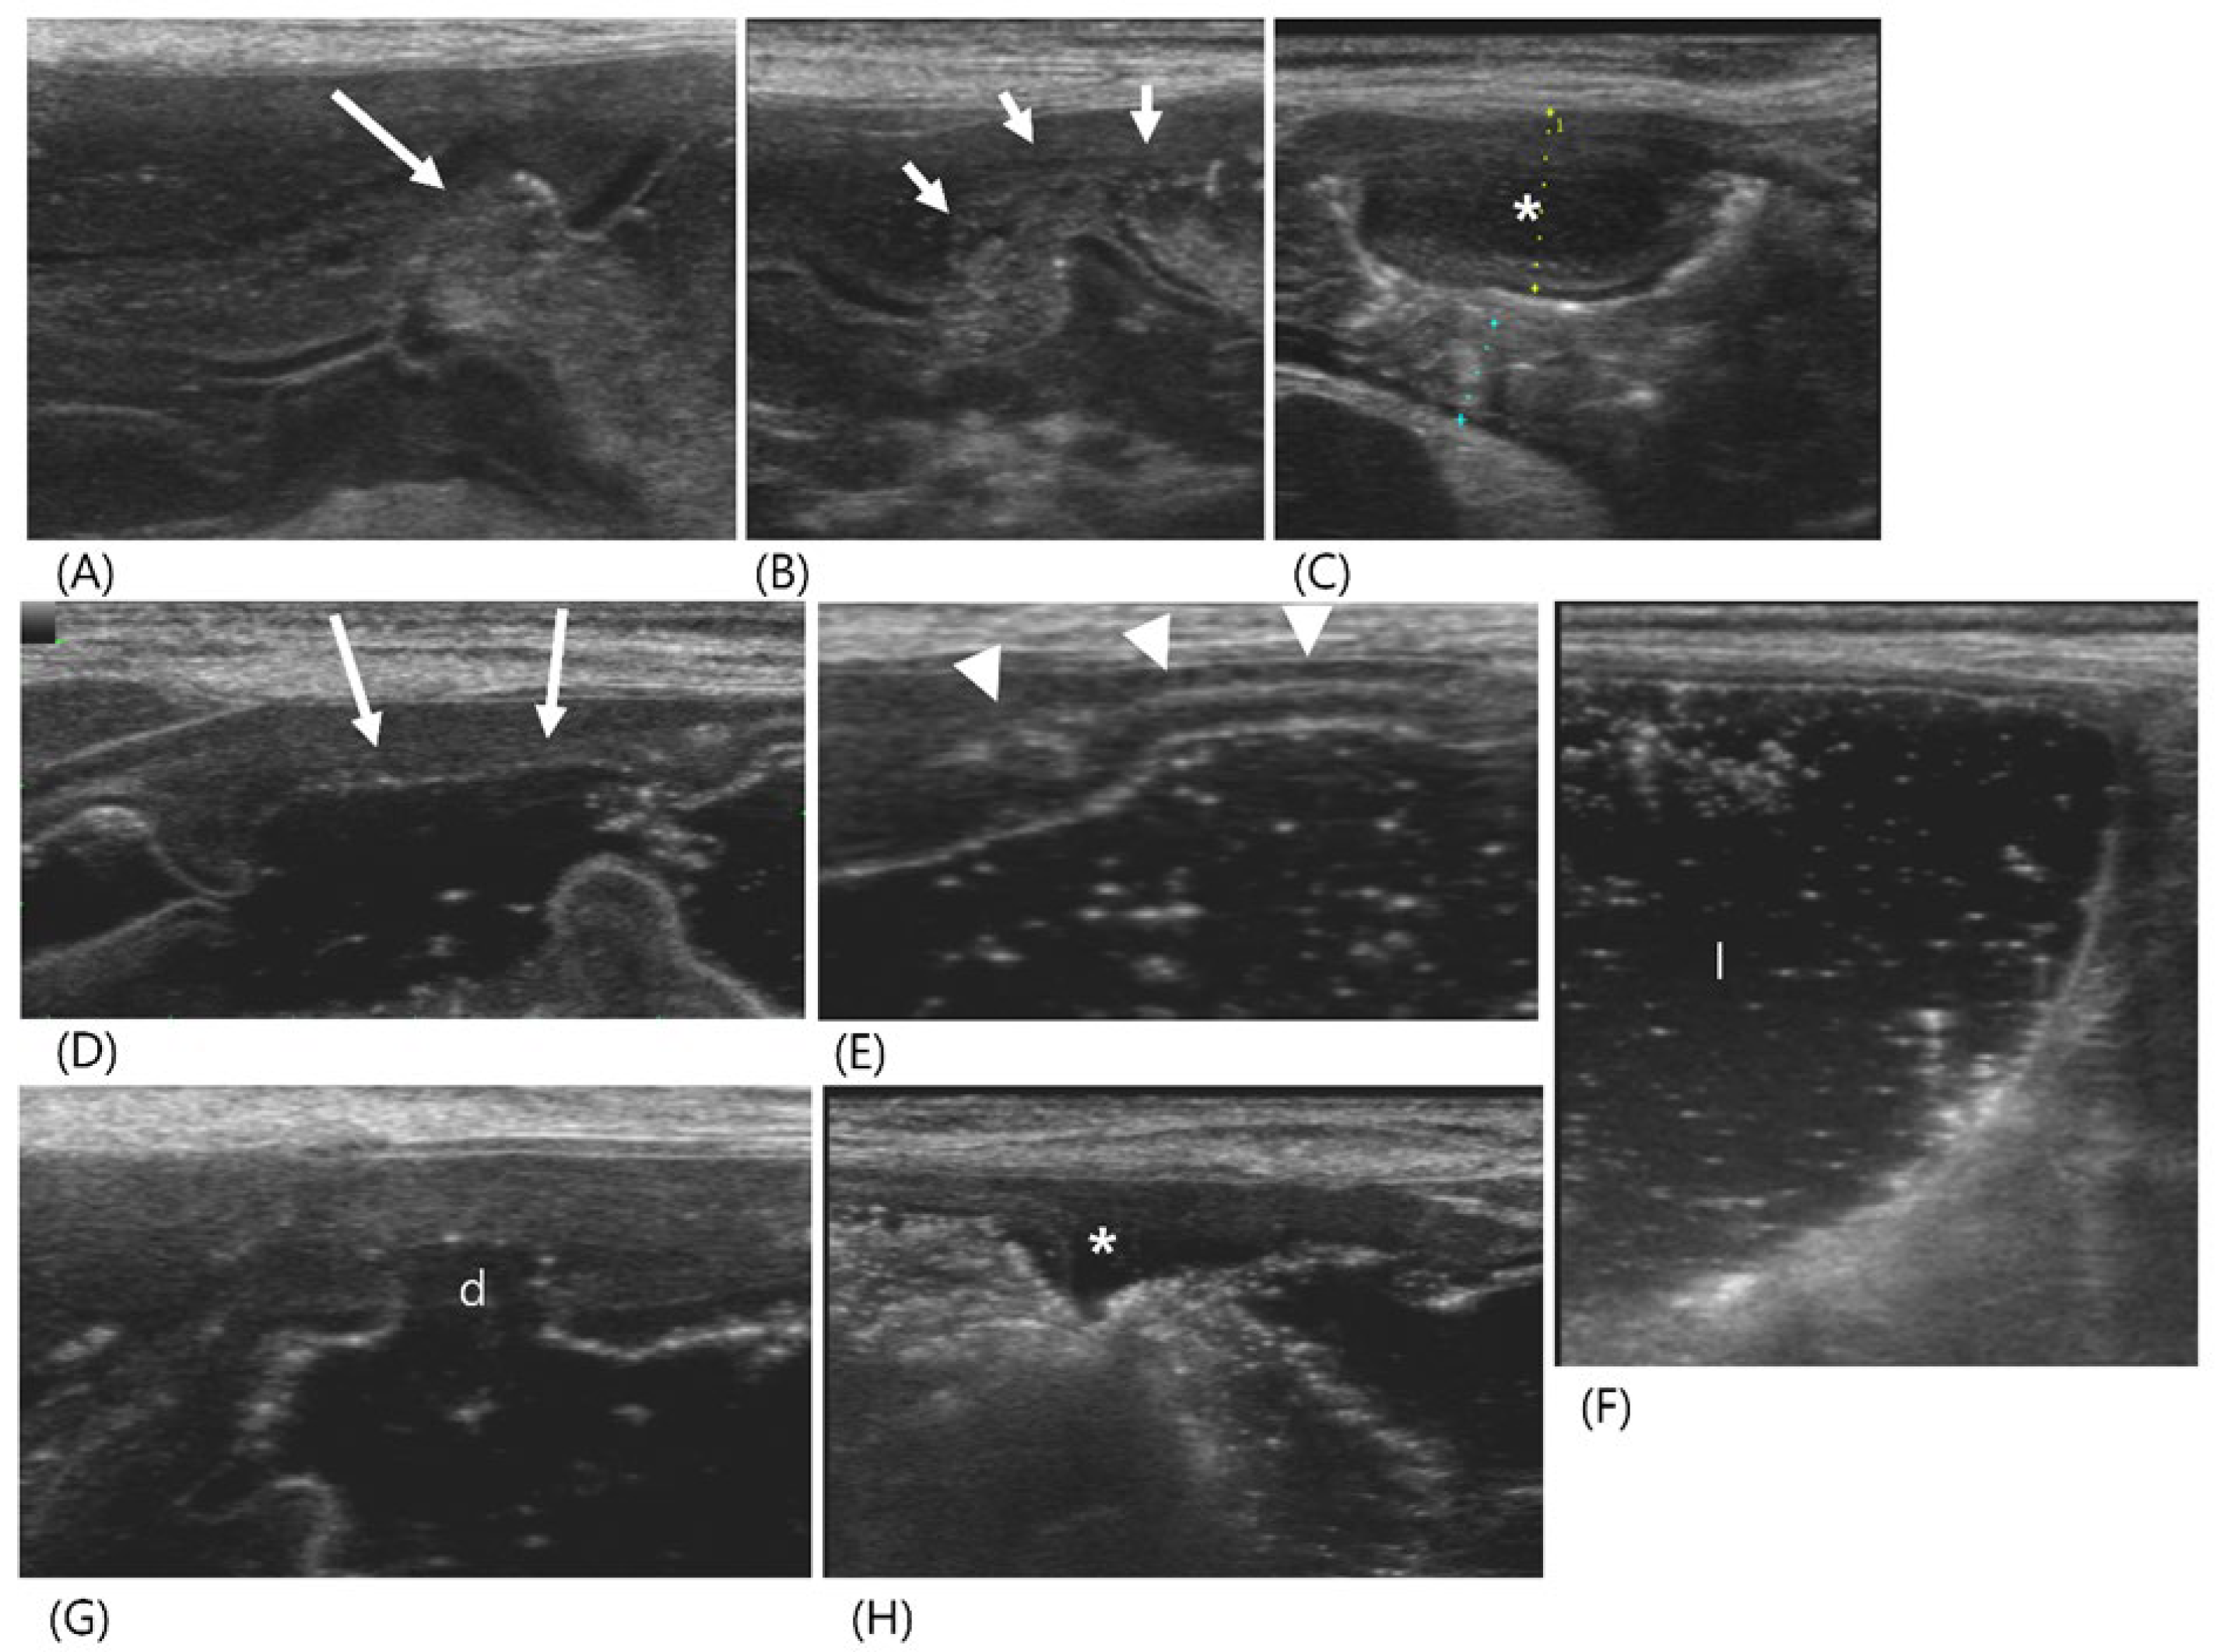

2.1. Case 1